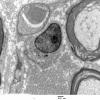

20D1 Suprascapular nerve (Case 20 EM 009A - Copy

20D2 Suprascapular nerve (Case 20) EM 016A - Copy

20D3 Suprascapular nerve (Case 20) EM 038A - Copy

20D4 Suprascapular nerve (Case 20) EM 079A - Copy

20D5 Suprascapular nerve (Case 20) EM 085A - Copy

20D6 Suprascapular nerve (Case 20) EM Neuroma_043A - Copy